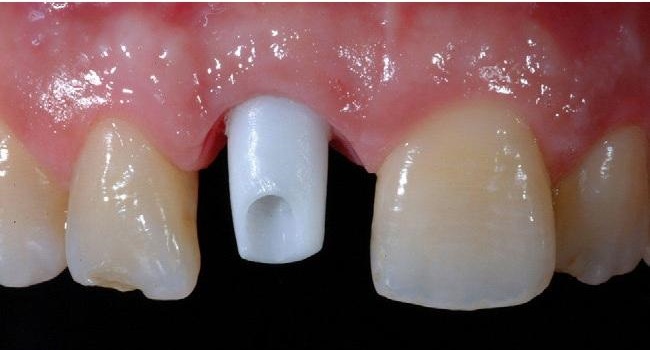

giải pháp trồng răng implant DCTHình ảnh tạo hình tái lập lợi và mô nha chu theo chuẩn giải phẫu nhờ sử dụng Healing Customized và định hình bằng Abutment Customized

Trồng răng implant cá nhân hóa

Hình ảnh lỗ lợi được tạo ra bởi trụ lành thương sản xuất sẵn và trụ phục hình sản xuất sẵn: bé, tròn, không theo hình thể giải phẫu